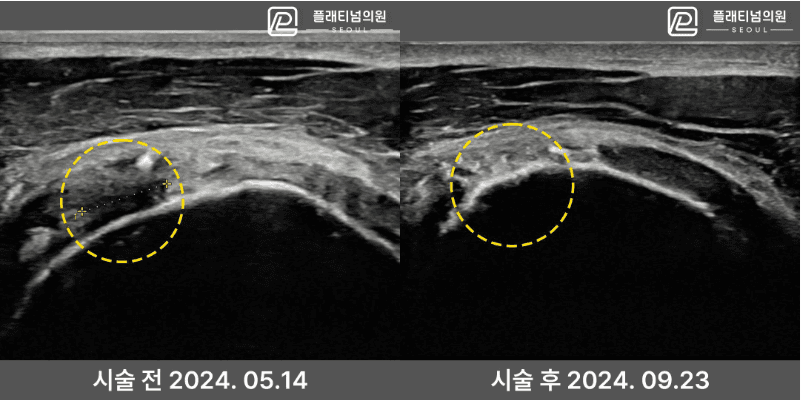

인대재생주사 시술 전후 초음파

실제 환자의 시술 전후 초음파 비교입니다. 파열되어 결손이 있던 인대 조직이 시술 후 회복된 것을 확인할 수 있습니다.

* 개인차가 있을 수 있으며, 모든 환자에서 동일한 결과를 보장하지 않습니다.